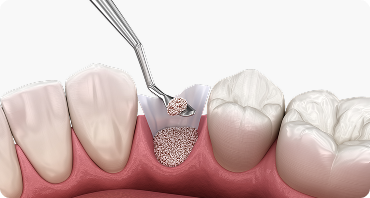

뼈이식 임플란트

임플란트에서 중요한 부분은 두꺼운 뼈와 건강한 잇몸에 있습니다.

뼈가 안 좋아 임플란트가 어려울 경우, 임플란트 식립을 위해

약해진 잇몸뼈를 이식하여 임플란트의 장기적인 수명을 향상시킵니다.

골 재건 및 식립 기반 형성

뼈 소실 정도와 형태에 따라 골이식을 시행해

임플란트가 튼튼한기반을 잡을 수 있도록 재건